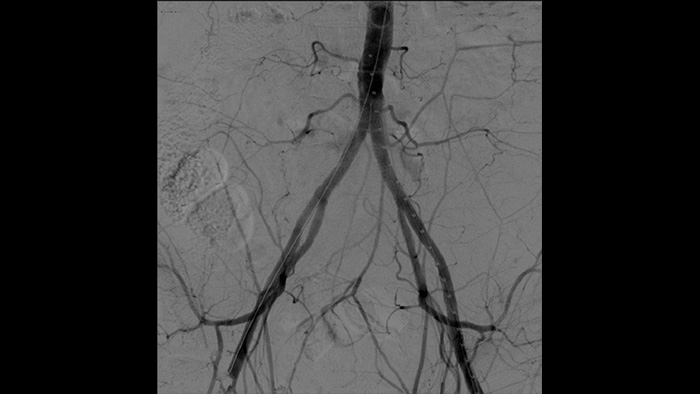

Dr. Ramon Vila ist auf dem Gebiet der minimal-invasiven Gefäßchirurgie einer der führenden Spezialisten Spaniens. Er ist außerdem Leiter der Abteilung für Angiologie und Gefäßchirurgie an der spanischen Universitätsklinik Bellvitge in Barcelona. Die Klinik führt jährlich 1000 gefäßchirurgische Eingriffe durch. Mit dem Philips Zenition mobilen C-Bogen erzielt Dr. Vila Bilder in hervorragender Qualität, dank derer er die meisten Gefäßeingriffe mit niedrigen Dosiseinstellungen durchführen kann.

„Mit dem Zenition hat sich unsere DSA-Bildqualität stark verbessert. Es gibt keine unscharfen Bilder mehr, nur noch sehr Klare.“

Ramon Vila Coll

MD, Universitätsklinik Bellvitge, Barcelona

Die digitale Subtraktionsangiographie (DSA) ist bei interventionellen Gefäßeingriffen besonders hilfreich. Bei diesem Verfahren werden Strukturen ausgeblendet, die Blutgefäße verdecken, um die Gefäße möglichst klar darzustellen. Zuvor unter Kontrastmitteleinsatz erfasste, subtrahierten Bilder werden mit dem Live-Durchleuchtungsbild überlagert (Roadmapping), sodass Sie Instrumente ohne erneute Kontrastmittelinjektion ungehindert verfolgen können.